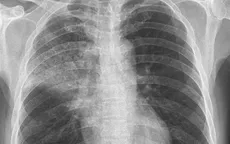

VTV.vn - Viêm phổi cộng đồng là bệnh nhiễm khuẩn đường hô hấp thường gặp ở mọi lứa tuổi, đặc biệt là những người có hệ miễn dịch yếu như người già, trẻ nhỏ, người có bệnh lý nền.